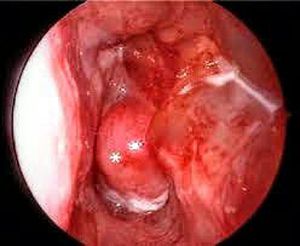

Nasopharyngeal angiofibroma !

Nasopharyngeal angiofibroma has the following features except: A. It is endemic in people of South-East Asia B. It occurs exclusively in adolescent males C. It is a benign nasopharyngeal tumour D. Testosterone hormone plays a role in its etiology

A